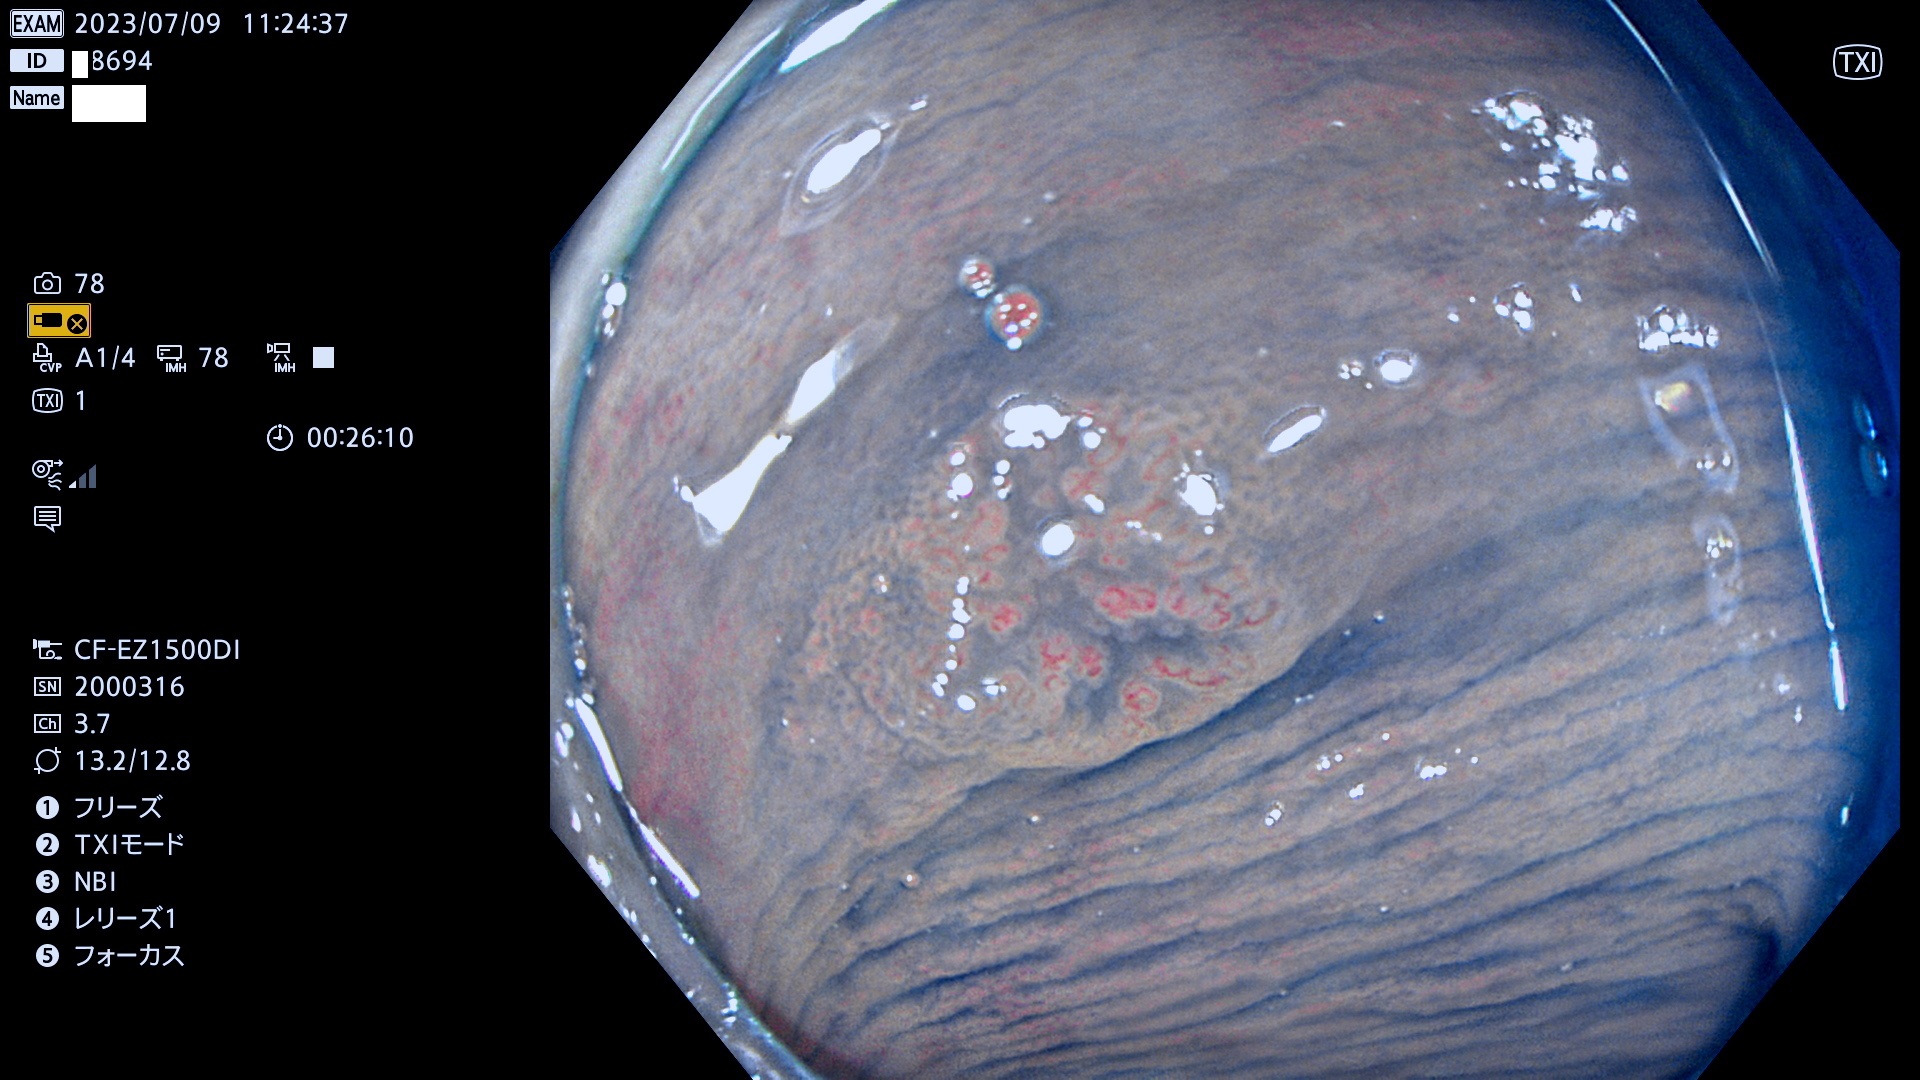

大腸Ub、Uc型・腺腫とは?

「表面型腺腫(Flat Adenoma)の中で、完全に平坦な物をUb、陥凹している物をUcと呼びます。平坦隆起型(Ua)よりも、発見が難しく危険な病変です。このタイプの発見率は「腺腫発見率」よりも、遥かに重要な意義があります。

抽出の対象期間 2023年7月6日(木)〜7月9(日)の4日間(48件の検査)6件